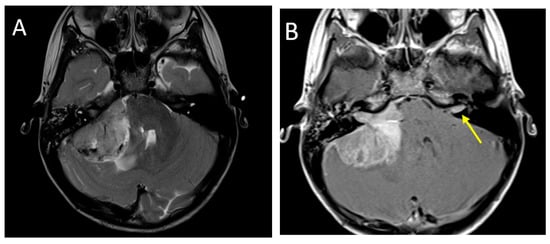

Figure 4.

A 2.5-year-old girl with AT/RT. Axial T2 (A), post-contrast T1 (B), images demonstrate a heterogeneous lesion in the right cerebellopontine angle extending into the internal auditory canal. There is also a metastatic lesion in the left IAC (arrow). DWI (C) and SWI (D) imaging demonstrate restricted diffusion and susceptibility common in these lesions.